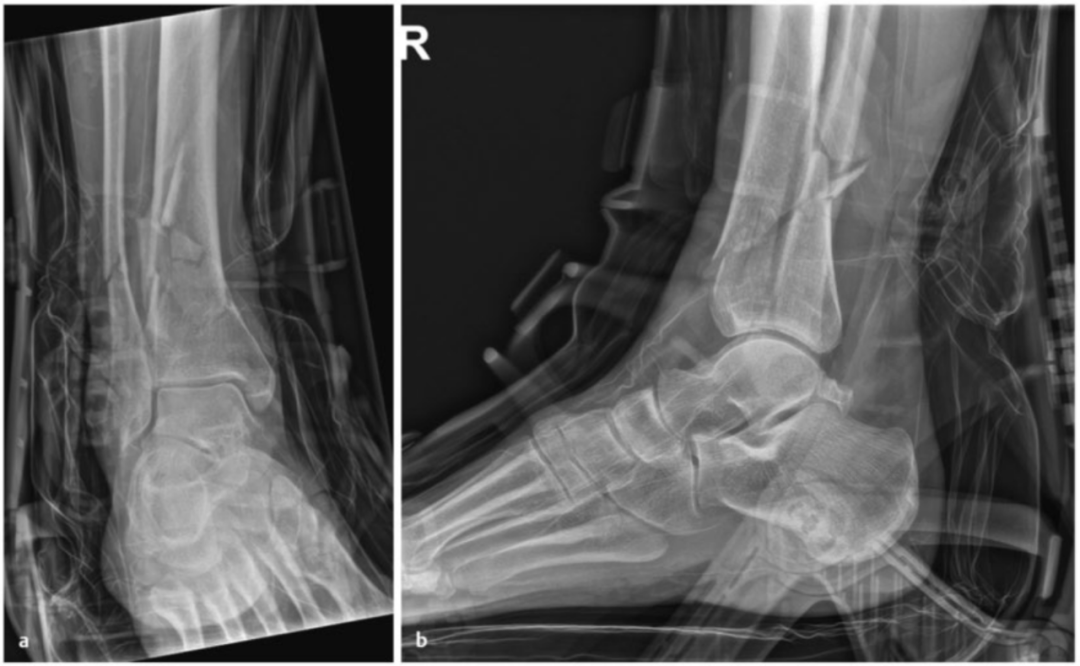

病例2受伤后入院首先植入跨踝关节外固定架,待软组织肿胀消退后,先对腓骨骨折进行微创固定,随后逐步完成复杂的胫骨Pilon骨折复位与固定。

术中临床图像显示了损伤的严重程度,同时体现了微创手术技术的优势,以及在必要时下胫腓联合切开复位重建的重要性。借助斯氏针的 “操纵杆(Joy-Stick)” 技术,可显著简化关节面的复位操作。

术后影像学随访检查显示骨折解剖复位,内植物位置良好。

患者术后恢复顺利,关节功能良好。术后12个月取出内植物,未发现创伤后关节炎征象。